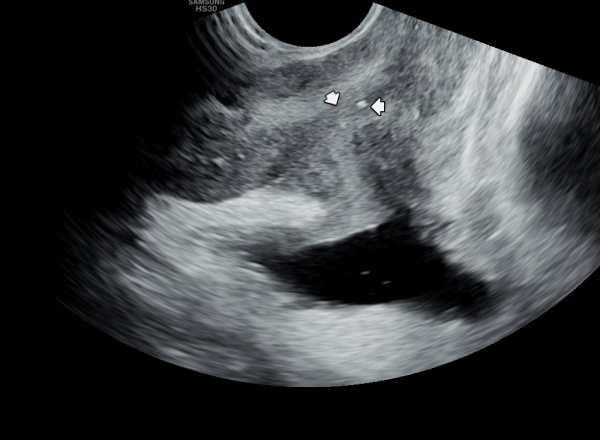

수년 전부터 배뇨중 타는 듯한 느낌의 작열 감과 배뇨 장애로 여러 비뇨기과에서 치료를 했으나 증상의 호전이 없어 내원 당일 검사한 경직장 전립선

초음파 검사 상 사정관 입구의 미세 결석과 사정관 낭종이 관찰되는 사진입니다.

A transrectal prostate ultrasound image taken on the day of the visit from a patient who had experienced a burning sensation during urination and voiding dysfunction for several years. Despite receiving treatment at multiple urology clinics, symptoms did not improve. The ultrasound shows microcalcifications and a cyst at the opening of the ejaculatory duct.

내원 당일 경직장 전립선 초음파 검사중 사정관 내에 미세 결석이 관찰되는 초음파 사진입니다.

A transrectal prostate ultrasound image taken on the day of the visit shows microcalcifications within the ejaculatory duct.